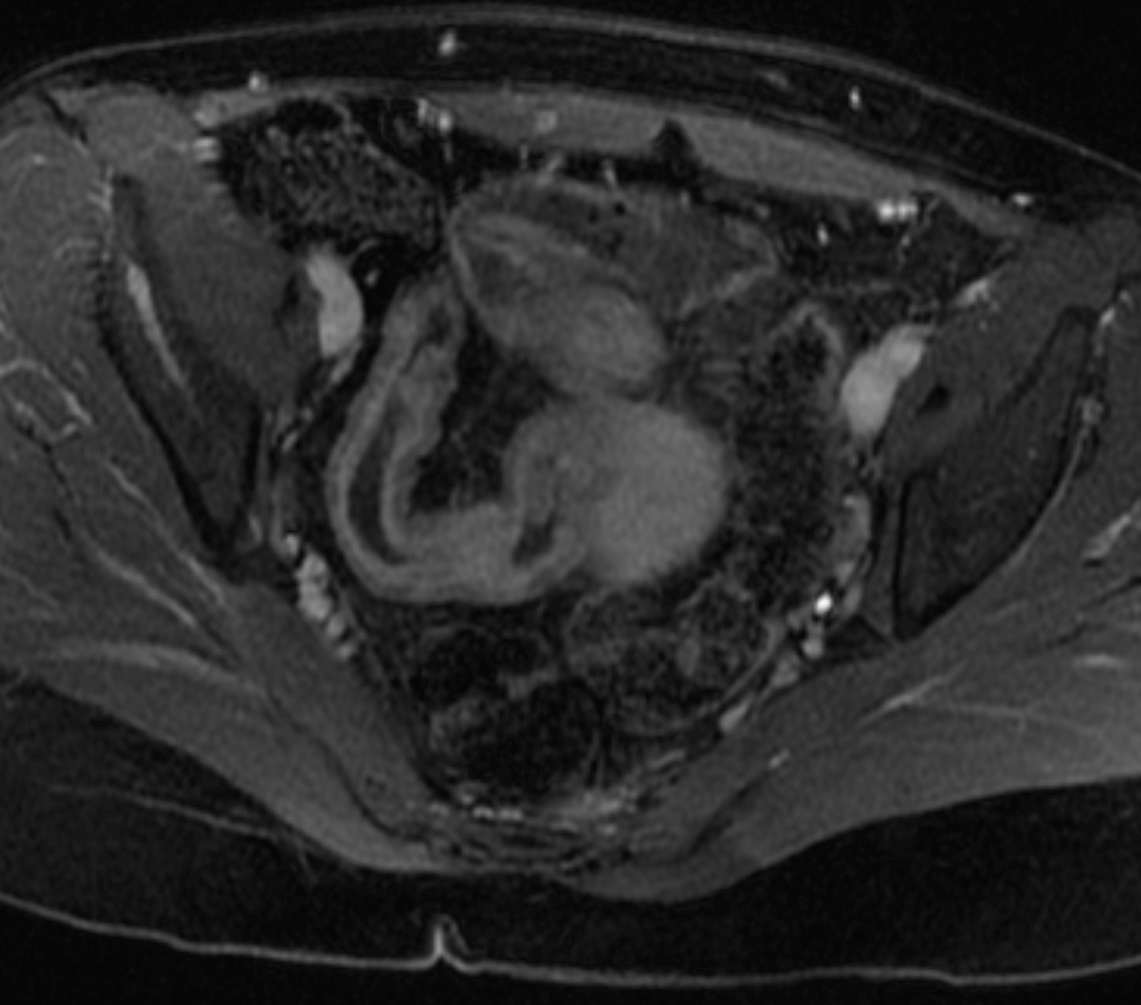

MR enterography is valuable for determining extent of inflamed bowel, discriminating between active inflammation and chronic fibrosing disease, detecting fistulae, and detecting strictures. Additionally, MRI can provide excellent delineation of the course of perianal fistulas, including relationships to sphincters and levators.

Before undergoing MRI to evaluate the bowel, one drinks a little over one quart of a fluid that helps to distend the bowel, and an intravenous catheter is placed so that intravenous contrast can be administered.